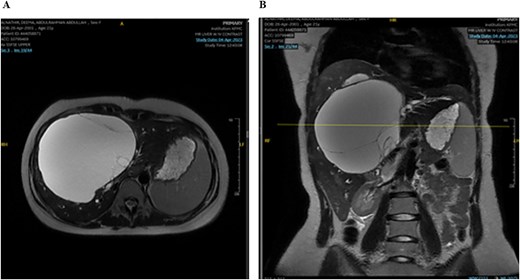

Laboratory studies were performed for serum alpha-fetoprotein (AFP), carcinoembryonic antigen (CEA), and carbohydrate antigen (CA). All the above investigations were normal except for an elevated level of CA-19.9. A computed tomography (CT) of the abdomen and chest with an intravenous contrast scan was performed. Chest imaging did not reveal any malignancy. Abdominal imaging demonstrated a big, multiseptated hepatic cystic mass, measuring 14 × 11 × 16 cm, involving segments 4A, 4B, 5, 6, and 8, shown in Fig. 1.

CT scan of the abdomen: Demonstrating the hepatic mass measuring involving the segments 4A, 4B, 5, 6, and 8. A) Transverse view, B) longitudinal view.

The mass had fine, minimally enhancing septations without any solid enhancing component. Communication with the right intrahepatic biliary ducts was observed, leading to moderate intrahepatic biliary duct dilatation. Magnetic resonance imaging (MRI) of the liver using contrast reveals a large hepatic cystic mass, corresponding to dimensions noted on CT, showing bright T2 signal intensity with thin septations without a solid component, illustrated in Fig. 2.